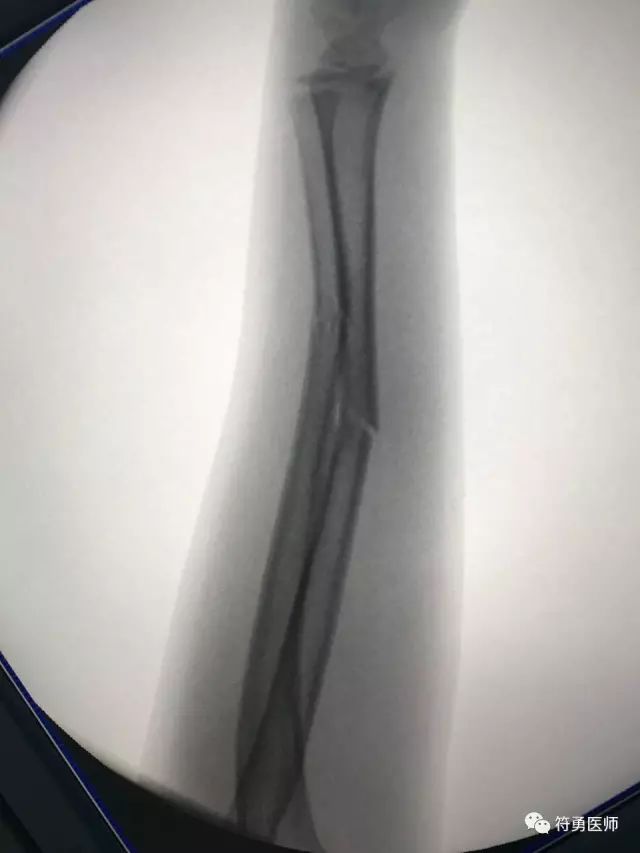

上图:经过南华附二小儿骨科中心精心复位接骨之后,位置完美。

采用祖国医学五千年经典神奇手法接骨,借鉴西医新时代先进顶尖理念复位,在三维C臂动态检测下,成功给孩子复位接骨,并采用独特的手法及三点衬垫固定技术,不开刀,不手术,纯手法,接骨成功。

原本需要花费4万多元微创手术才能解决的问题,我们只用两千多元搞定。给孩子和孩子父母家人一份满意惊喜的答卷。